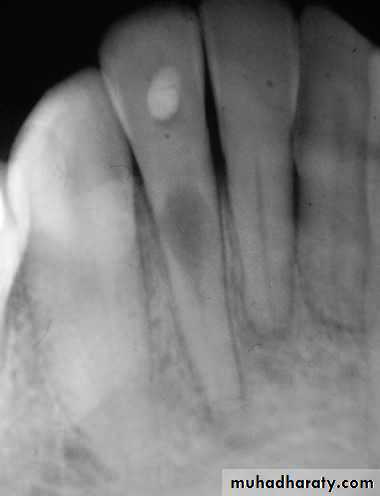

*The No. and curvature of root canals may need modification of outline form & to avoid scarifying of tooth structure.2.Preoperative radiograph: Give great information about status, shape and size of pulp chamber.

Radiographs in Endodontics*Initial radiograph: Diagnosis. *Working length film: Used to determine the length of the canal. *Final instrumentation film: Taken with the final size files in all canals. *Root canal completion film: Taken after the tooth as been temporized. *Recall films: Taken at evaluations.

Requirements of Endodontic Films *Show 4-5 mm beyond the apex of the tooth and the surrounding bone or pathologic condition. *Present an accurate image of the tooth without elongation or fore-shortening. *Exhibit good contrast so all pertinent structures are readily identifiable.